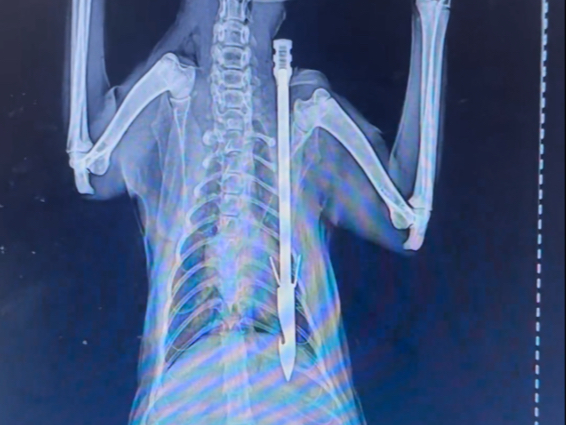

Kung Fu macam apa ini? Tanganku patah hanya dengan satu pukulan!